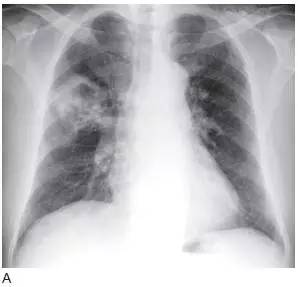

图3 鳞状细胞癌伴空洞

A. 胸片显示右上叶大的厚壁空洞;

B.CT 显示厚壁空洞及壁结节,为恶性空洞的典型征象,属T2 期